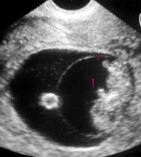

Bebeğinizin kol ve bacak taslakları bu

haftada hızlı bir gelişim sürecine girmiştir. Dizler, dirsekler, el ve ayak

parmakları da taslak halinde oluşmaya başlamıştır. Ayak ve el parmaklarında

tırnakların minicik taslakları ortaya çıkmaya başlar. Yüzde kulaklar, gözler

ve burun kökü oluşmaya başlar. Barsaklar henüz kordon içinde yeralmaktadırlar.

Dişetlerinin altında diş taslakları ortaya çıkmaya başlamıştır. Bebek bu

hafta içinde geçen haftaki büyüklüğünün iki katına ulaşmış olup, yaklaşık 2

gram ağırlığındadır.